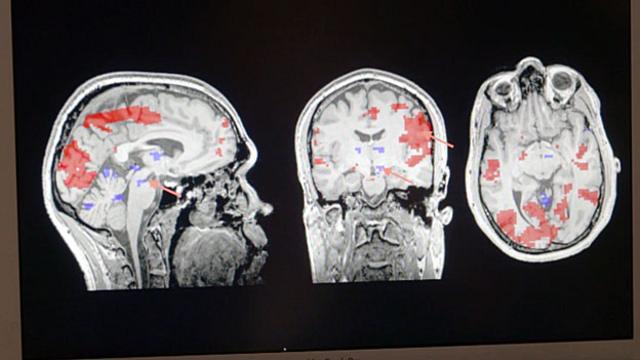

Xand van Tulleken ofereceu o irmão, Chris, para a ressonância magnética do cérebro (Foto: BBC)

E os resultados foram estes (Foto: BBC)

Ofereci meu irmão gêmeo, Chris, para fazer a ressonância magnética do cérebro com uma foto da esposa dele, Dinah, nas mãos. No exame ele demonstrou um perfil cerebral típicocasas de apostas e seus bonusuma pessoa apaixonada.

Uma região chamada área tegmental ventral, parte do circuitocasas de apostas e seus bonusprazer e gratificação do cérebro, estava muito ativa. E houve uma desativação do córtex pré-frontal dorsolateral, que controla o raciocínio lógico.

Estarcasas de apostas e seus bonusum estado a que os cientistas se referemcasas de apostas e seus bonusforma técnica como “amor romântico, apaixonado” faz com que você não pense com clareza. Neurologicamente falando, Chris era um tonto apaixonado.